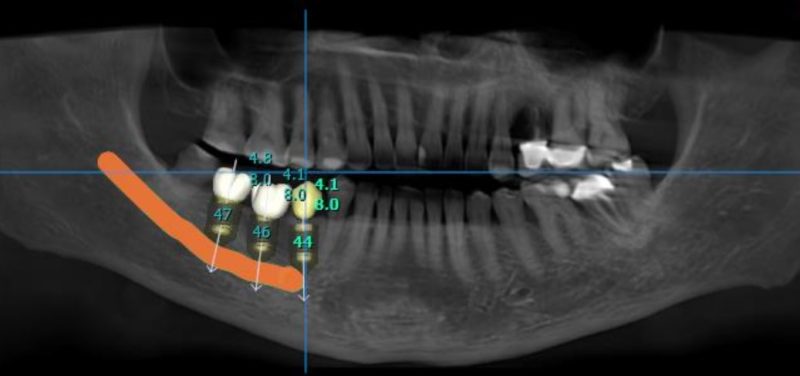

Good morning everyone, I would like to get your opinion on the following treatment options for this case. This patient has missing 47, 46 and a retained root at 45. Interocclusal space is about 5mm ( so i cannot perform vertical bone augmentation), bone height is limited, about 10mm ( close proximity to ID canal) and bone width is not satisfactory as well . I have not used any short implants with high engaging threads ( BLX implant) in my practice so I would like to get everyone’s input on this. Thank you.

Treatment plan 1 : 3 units straumann BLX implants ( 45 : 3.75mm x 6mm, 46 : 3.75mmx6mm, 47: 4.5mmx6mm) + GBR with autogenous and straumann xenograft + 3 units splinted final prosthesis

Treatment plan 3 units straumann BLT implant (45 : 4.1mm x 8mm, 46 : 4.1mmx8mm, 47: 4.8mmx8mm) + GBR with autogenous and straumann xenograft + 2 units splinted 46,47 and single unit 45 final prosthesis

More lingual placement on 47 and site 45 looks very narrow so may have the most predictable outcome performing GBR in area prior to placement and I would go with shorter implants to allow more subcrestal placement which will also allow more restorative space. I also typically prefer individual implants but in this case an implant bridge may make more sense for the pt. And/or minimize treatment for patient as the middle site has the least bone width.

Thanks for the post William! I think in this case, you should plan a GBR like @restoredsmiles suggested. Also, the shorter implants are the way to go here so you still have 2mm safety zone before the nerve canal!